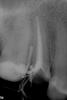

Ashley Опубликовано 11 мая, 2010 Поделиться Опубликовано 11 мая, 2010 (изменено) Здравствуйте! Очень прошу оценить качество работы (состояние каналов и т.д.) по моим снимкам. 24 апреля я обратилась в клинику из-за скола в зубе (5 зуб на верхней челюсти). Каналы были прочищены, в зуб был вставлен штифт из титана. Зуб был сточен очень сильно, на него налеплена светоотверждающая пломба. Спустя 2 недели я немного простудилась и в зубе начались ноющие боли, боль отдает в ухо, ноет даже ночью. Симптомы простуды практически прошли, есть легкая заложенность носа, на ночь выпила парацетомол, сегодня проснулась с температурой и ноющей болью в зубе. Как может быть связана простуда с болью в зубе? Также есть боль в десне над зубом. И при надкусывании очень неприятные ощущения - как будто я чувствую, что внутри движется штифт. Доктор, которая лечила меня, сказала, что все это из-за простуды, а на снимке все прекрасно. Сказала - лечитесь, будем наблюдать, боли должны пройти. Если не пройдут - будем перелечивать каналы. Я уже поняла, что если боль будет продолжаться, значит, каналы нужно будет перелечивать. Сейчас каналы запломбированы Сеалапекс + гуттаперчивые штифты. В корне - штифт металлический на фосфат-цементе. Пожалуйста, посмотрите, как сделана эта работа, как запломбированы каналы, как стоит штифт. Можно ли такой штифт достать? Врач уверяет, что такой зуб мне должен прослужит 8 лет, что штифт , аккуратно вкученный ею в корень, не может сломать корень, что каналы она вылечила прекрасно, а до этого там было скопище микробов. Прочитав подобные темы на сайте, я поняла, что лучше сделать вкладку с коронкой. Правильно ли я поняла? Очень прошу высказать свое мнение по поводу моей ситуации. Прилагаю снимки зуба до лечения и после лечения. Изменено 11 мая, 2010 пользователем Ashley Ссылка на комментарий

Ashley Опубликовано 11 мая, 2010 Автор Поделиться Опубликовано 11 мая, 2010 А это снимок зуба, сделанный вчера, когда я снова обратилась к врачу с вопросом о причине боли. Ссылка на комментарий

x3m Опубликовано 11 мая, 2010 Поделиться Опубликовано 11 мая, 2010 Каналы были прочищены, в зуб был вставлен штифт из титана. Зуб был сточен очень сильно, на него налеплена светоотверждающая пломба. нужна коронка и ВКВ, а не анкер и фотополимер. ...в зубе начались ноющие боли, боль отдает в ухо, ноет даже ночью. т.к. есть второй канал. Это хорошо видно на контрольном (вчерашнем) снимке.Оценить, как установлен штифт - невозможно. Его не видно на снимке.Анкера хорошо достаются. Главное, чтобы доктор умел это делать и имел ультразвуковой наконечник. зы. а что по прошествии восьми лет с зубом будет? о прогнозах спросили? Ссылка на комментарий

Мартовский Опубликовано 11 мая, 2010 Поделиться Опубликовано 11 мая, 2010 нужна коронка и ВКВ, а не анкер и фотополимер.т.к. есть второй канал. Это хорошо видно на контрольном (вчерашнем) снимке.Оценить, как установлен штифт - невозможно. Его не видно на снимке.Анкера хорошо достаются. Главное, чтобы доктор умел это делать и имел ультразвуковой наконечник. зы. а что по прошествии восьми лет с зубом будет? о прогнозах спросили?Я бы не был столь категоричен. Во-первых не все врачи являются приверженцами вкладок, и нет стандарта, в котором было бы написано "на депульпированный пятый обязательно вкладку и коронку". И уж тем более не это причина боли. Во-вторых я не вижу на снимке второго пустого канала. Т.е. может он там и есть, но по такому снимку мы это навряд ли определим. В пятёрках часто бывает по одному щелевидному каналу с раздвоенной верхушкой. В третьих обострение после перепломбировки очень даже вероятно, если ещё простуда наложилась, то может просто совпасть, и усилить симптомы.То качество пломбирования, которое мы видим, вполне соответствует стандартам.///Сказала - лечитесь, будем наблюдать, боли должны пройти. Если не пройдут - будем перелечивать каналы./// Я бы тоже так сказал, не надо горячку пороть. Если хотите удостовериться в качестве лечения, сделайте контрольный снимок через пол-года. Сделайте в независимости от симптоматики, и вывесите, а мы скажем, есть у вас проблема, или нет. Ссылка на комментарий

x3m Опубликовано 12 мая, 2010 Поделиться Опубликовано 12 мая, 2010 Я бы не был столь категоричен. Во-первых не все врачи являются приверженцами вкладок, и нет стандарта, в котором было бы написано "на депульпированный пятый обязательно вкладку и коронку". эммм... я так... думаю. (с)"Мимино" ессно, нету стандартов, что на депульпированный пятый надо обязательно ВКВ и коронку. НО. на контрольном снимке (после пломбировки каналов с пучком гутты) есть все показания для ВКВ и коронки, а не для анкера с лепкой композитом... или нет? в этом случае вопрос не в религии и склонности докторов к анкерам/ВКВ. А в присутствии отсутствия достаточного массива твердых тканей. Что есть клиническим показанием для вышеизложенной техники восстановления. а к качеству пломбировки одного канала претензий нет. все хорошо. по поводу второго канала - я его увидел вот здесь:http://i061.radikal.ru/1005/e5/7c7363b88f90.jpghttp://s006.radikal.ru/i213/1005/79/997e7c291cb1.jpg периодонтальная щель второго корня и отдельный апекс имеютЦа. Поиграться бы с ангуляцией - избежали бы наложения. Ashley, попросите врача поменять угол рентгенсъемки, "сфоткать" зуб под другим углом. Ссылка на комментарий

Мартовский Опубликовано 12 мая, 2010 Поделиться Опубликовано 12 мая, 2010 эммм... я так... думаю. (с)"Мимино" ессно, нету стандартов, что на депульпированный пятый надо обязательно ВКВ и коронку. НО. на контрольном снимке (после пломбировки каналов с пучком гутты) есть все показания для ВКВ и коронки, а не для анкера с лепкой композитом... или нет? Я бы с вами поговорил об этом, но не в этом разделе. Что касается второго канала, то его на РВГ можно обнаружить только сделав несколько снимков в разных проекциях. Две верхушки я и сам вижу, поэтому и написал ///В пятёрках часто бывает по одному щелевидному каналу с раздвоенной верхушкой./// Ну и согласитесь, обострение после пломбирования, не такая уж редкая вещь. Ссылка на комментарий

x3m Опубликовано 12 мая, 2010 Поделиться Опубликовано 12 мая, 2010 Я бы с вами поговорил об этом, но не в этом разделе....Ну и согласитесь, обострение после пломбирования, не такая уж редкая вещь.о показаниях? давайте поговорим.Обострения бывают, согласен... Но пульпитообразная симптоматика - очень уж напрягает. Ну не похоже это на периапикальные реакции, верно? И через 2 недели после пломбировки...А если есть остаточные симптомы от нераскопанных каналов плюс рентгенподтверждение - их надо раскапывать вне зависимостей от уровня ответвления. Ссылка на комментарий